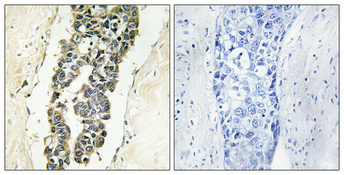

ApplicationsELISA, ImmunoHistoChemistry

ReactivityHuman, Mouse, Rat

ApplicationsELISA, ImmunoHistoChemistry

ReactivityHuman, Mouse, Rat

ApplicationsELISA, ImmunoHistoChemistry

ReactivityHuman, Mouse, Rat

ApplicationsELISA, ImmunoHistoChemistry

ReactivityHuman, Mouse, Rat